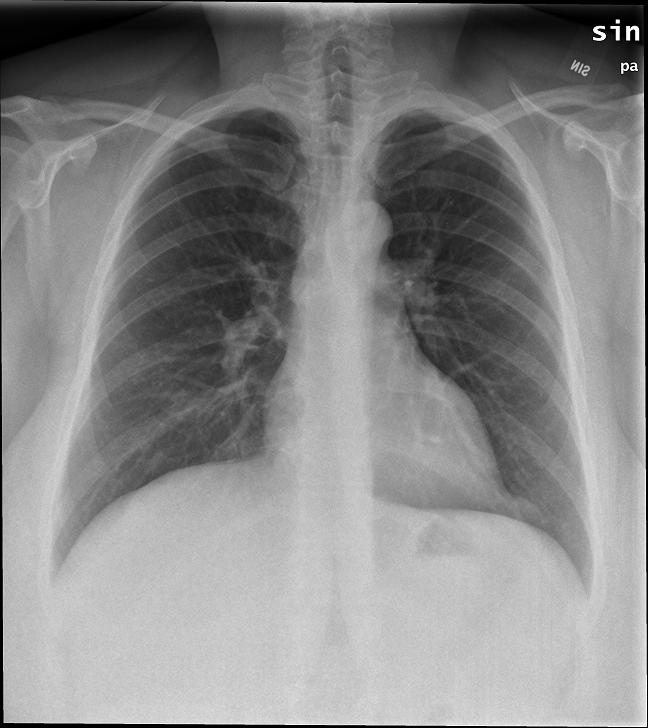

解剖学模块